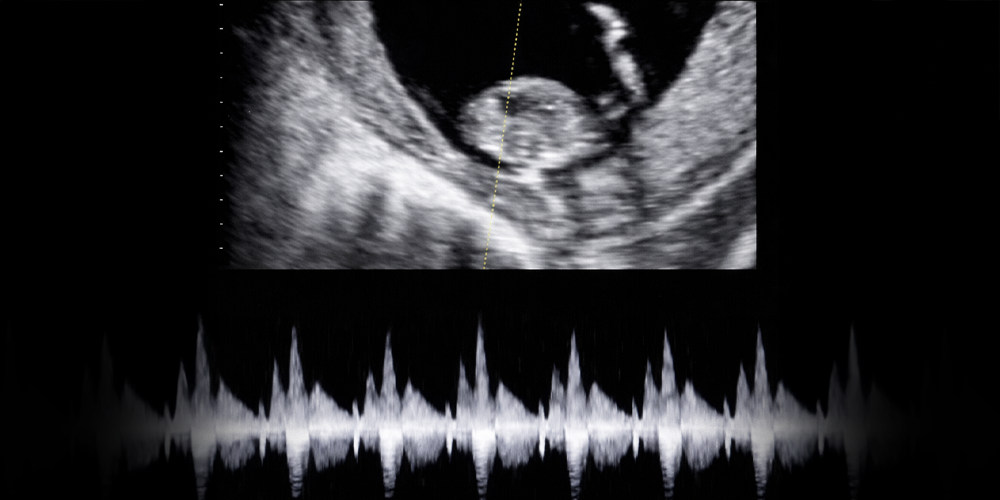

İlk Kalp Atışı

Bu dönemde kalp atışları ultrasonda görülebilir ve duyulabilir.